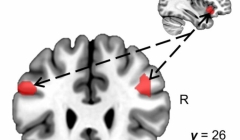

Studio rivela dove vengono memorizzati i frammenti di memoria

22.07.2022 | Ricerche

Un momento indimenticabile in un ristorante può non essere esclusivamente il c...